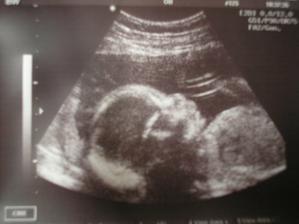

Daníček se narodil 28.12.2007 v 0:40 císařským řezem, vážil 4,53kg a měřil 53cm, žádnej drobeček to nebyl a není, papá jako o závod a váha přibývá a přibývá....🙂)